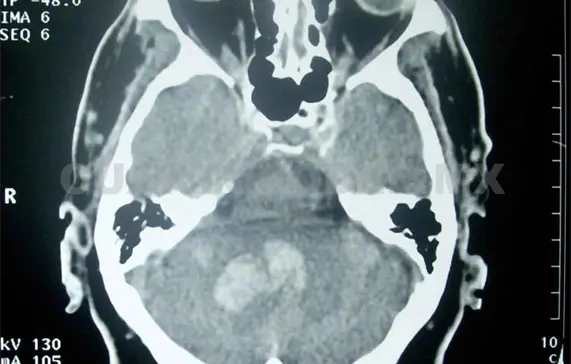

De acuerdo al Centro Nacional de Neurología y Neurocirugía “Manuel Velasco Suárez”, existen tres tipos de EVC: trombótico, embólico y hemorrágico; el primero se origina por los depósitos grasos en las arterias, lo que causa la formación de coágulos como consecuencia del estrechamiento de los vasos sanguíneos.

En el caso del EVC embólico, el coágulo se forma en otras partes alejadas del cuerpo, parte de esa formación conocida como “émbolo” es arrastrado hacia el cerebro hasta que tapa un vaso sanguíneo y corta el abastecimiento de sangre ocasionado una embolia.

Por último está el tipo hemorrágico o derrame cerebral, causado por la ruptura y sangrado de un vaso sanguíneo en el cerebro. En todos los casos las señales de alarma, además de las que enlistó doña María, son visión borrosa, mareos repentinos, dolor de cabeza intenso e incapacidad para comunicarse de cualquier forma.